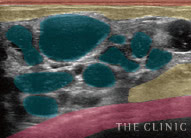

しこりの多発

しこり多発の原因は定かではありませんが、注入回数や体の中で流れることもあるヒアルロン酸の性質との関係性が考えられます。この症例もヒアルロン酸を繰り返し注入した方でした。

しこりの数

ヒアルロン酸豊胸では、しこりが複数できるケースも多々あります。あまりに多いと、1日で取り切るのが難しいことも。取り残しを防ぐ他、施術計画の意味でもこのチェックが必要です。